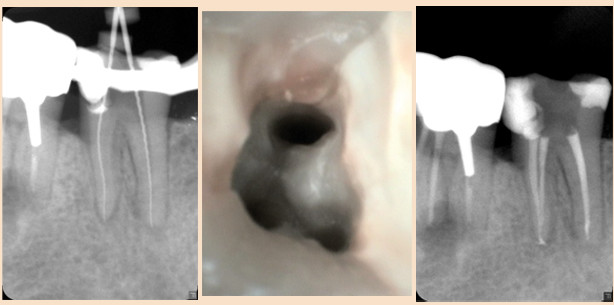

Dieser Patient kam mit starken Beschwerden im linken Unterkieferseitenzahnbereich zu uns. Der Zahn 37 war leicht perkussionsempfindlich und reagierte negativ auf die Vitalitätsprobe. Nach einer Leitungsanästhesie und dem Anlegen des Kofferdams wurde der Zahn 37 trepaniert und das Pulpenkavum und die Wurzelkanaleingänge dargestellt. Da ein Orthopanthogramm (OPTG) bereits vorhanden war, wurde zur Bestimmung der vorläufigen Arbeitslänge und der eindeutigen klinischen Symptome auf ein erneutes Röntgenbild verzichtet. Die Wurzelkanäle wurden mit Handinstrumenten bis ISO 20 aufbereitet und eine Röntgenmessaufnahme angefertigt (Abb. 11). Dabei zeigt sich eine leichte Überinstrumentierung der Kanäle, was klinisch nicht zu erkennen war. Die Kanäle wurden mesial mit R25 und distal mit R40 bis ins apikale Drittel aufbereitet und nach dem bekannten Protokoll gespült. In diesem Fall wurde die NaOCl-Spülung mit Ultraschall unterstützt. Es folgten eine medikamentöse Einlage mit CaOH und der provisorische Verschluss mit Cavit. In der folgenden Sitzung wurde nach einer Anästhesie und dem Anlegen des Kofferdams die Aufbereitung der Kanäle mit der korrigierten Arbeitslänge abgeschlossen (Abb. 12). Die Wurzelfüllung erfolgte wiederum thermoplastisch (Abb. 13).